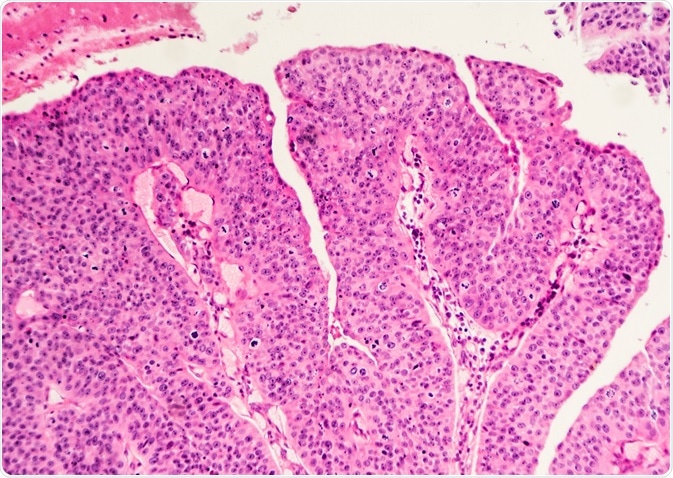

Bladder Cancer Histopathology

Histopathology provides a vast amount of valuable information about bladder cancer, such as the type, stage and grade of the cancer. This enables doctors to assess patient prognosis, best treatment options and possible specific therapies.

Image Credit: David Litman / Shutterstock